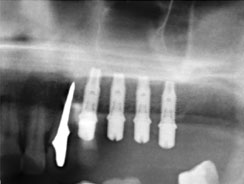

Одноэтапная имплантация